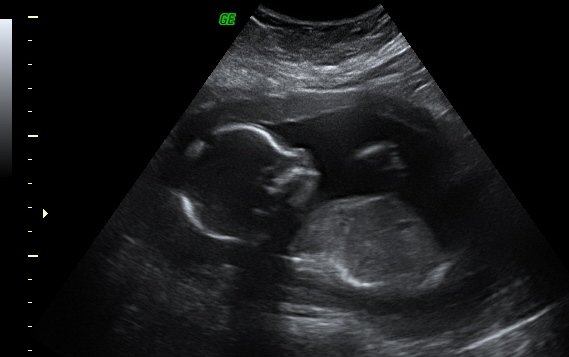

結果說好要寫第六次懷孕的續集,一拖就是將近半年後。 雖然已經離懷孕好久了,但還是要把紀錄寫好。 在美國確定心跳後,雖然不和台灣一樣會發一本媽媽手冊,但是相同的, 有看到心跳後才是正式的確認懷孕的旅程 ~ 基本上,沒有”重大”懷孕問題或紀錄的準媽媽們,在第一和第二產期間所需要回診的次數並不多。就是照著標準流程走,產科通常會提醒準媽媽什麼時候要回去產檢。 但是因為我懷孕失敗的紀錄輝煌,我的產檢是每週一次! 對! 你沒看錯,每週一次! 有禍必有福,也因為如此,在懷孕的第一到五個月我可以週週看到和聽到寶寶的心跳。...